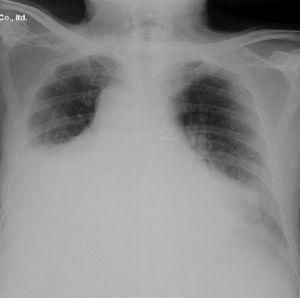

The chest X-ray showed cardiomegaly on admission, with no other findings. A few days later the patient presented an associated bilateral pleural effusion, predominantly on the left side (Fig. 1). A CT of the chest and abdomen reported a pericardial and pleural effusion, moderate in amount and of free morphology, causing a passive collapse of the basal segments of both lower lobes with the rest showing no abnormalities.2

Clinical improvement was evident in the first 48h, with increased mobility and a clear decrease in rigidity, especially at the level of the shoulder girdle, with the patient being able to walk. Likewise there were decreased inflammatory markers and the X-rays showed a marked decrease of the pleural effusion. The echocardiography performed after one month showed that the pericardial effusion had completely disappeared with only a slight right pleural effusion.